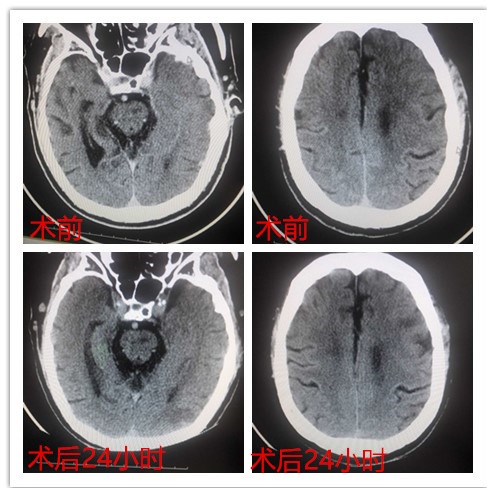

10月27日及31日,我院急诊科先后接诊两例急性中动脉堵塞脑血栓患者,梗塞面积大,伴有失语、面瘫、肢体瘫痪等症状,患侧肌力为0,病情十分严峻。急诊科接诊后,主任马永才当机立断,通知开通卒中绿色通道,经患者家属同意后由马永才、汤天津、鄂永军等医生行介入取栓治疗。紧张的手术过后,取栓成功。术后患者意识清晰,理解能力、言语能力恢复正常,其中一位患者在术后48小时肢体肌力便迅速恢复到五级,现均已康复出院。

据悉,机械取栓有较高的血管再通率,且临床禁忌症少,是近年国际上新出现的急性脑梗死血管再通方法,但是技术难度大,需要在脑梗死后尽快完成手术。这不仅需要医生高超的技术能力,更是对医务人员临场应变能力的考验。抢救过程中,我院行动火速,3小时内成功取栓,各科室配合默契,卒中绿色通道开辟及时,分秒必争,医护人员凭借着精湛的医技,与死神进行了一场惊险的较量,为患者日后的康复、提高生活质量,在时间上、技术上打了一场胜仗,也为医院下一步卒中中心的成功建立打下坚实基础。